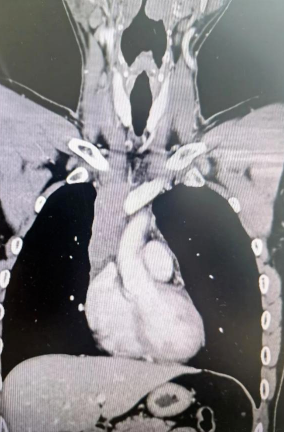

經(jīng)檢查發(fā)現(xiàn)患者前上縱隔腫瘤已經(jīng)完全侵犯了我們?nèi)梭w最主要的大靜脈之一——上腔靜脈,導(dǎo)致上腔靜脈回流嚴(yán)重受阻并導(dǎo)致由上腔靜脈起至左側(cè)無名靜脈、右側(cè)鎖骨下靜脈、右側(cè)頸內(nèi)靜脈等多根自上往下回流的靜脈阻塞,從而形成了廣泛的栓子,牢牢堵住了要流回心臟的血流,只能靠別的一些側(cè)支循環(huán)超負(fù)荷的工作,這也就是為什么孫先生脖子甚至是頭都明顯腫起來的原因。

4月30日,麻醉完成后,縱劈胸骨顯露右上縱隔腫瘤,發(fā)現(xiàn)腫瘤侵入上腔靜脈起始部,右鎖骨下靜脈及右頸內(nèi)靜脈血栓形成并向遠(yuǎn)端延伸。劉志主任團(tuán)隊(duì)將切口向右頸部延長(zhǎng),顯露右側(cè)頸內(nèi)靜脈至下頜角水平。張金洲副院長(zhǎng)團(tuán)隊(duì)經(jīng)股動(dòng)靜脈和左無名靜脈建立體外循環(huán)。在阻斷左無名靜脈遠(yuǎn)端后,李文海副院長(zhǎng)團(tuán)隊(duì)完整切除縱隔腫瘤及部分上腔靜脈、左無名靜脈、右鎖骨下靜脈和右頸內(nèi)靜脈切除。張金洲副院長(zhǎng)團(tuán)隊(duì)實(shí)施了無名靜脈近端、右鎖骨下靜脈和右頸內(nèi)靜脈內(nèi)血栓取出術(shù),并完成了左無名靜脈、右頸內(nèi)靜脈和右鎖骨下靜脈的人工血管置換手術(shù)。歷時(shí)6小時(shí),三個(gè)外科團(tuán)隊(duì)在麻醉科柴偉主任團(tuán)隊(duì)、體外循環(huán)團(tuán)隊(duì)以及食管超聲和手術(shù)室協(xié)作下,手術(shù)獲得成功。

術(shù)后患者經(jīng)過心外監(jiān)護(hù)室和胸外監(jiān)護(hù)室的接力治療,目前患者恢復(fù)順利,顏面部腫消失。復(fù)查增強(qiáng)CT三條人工血管通暢。